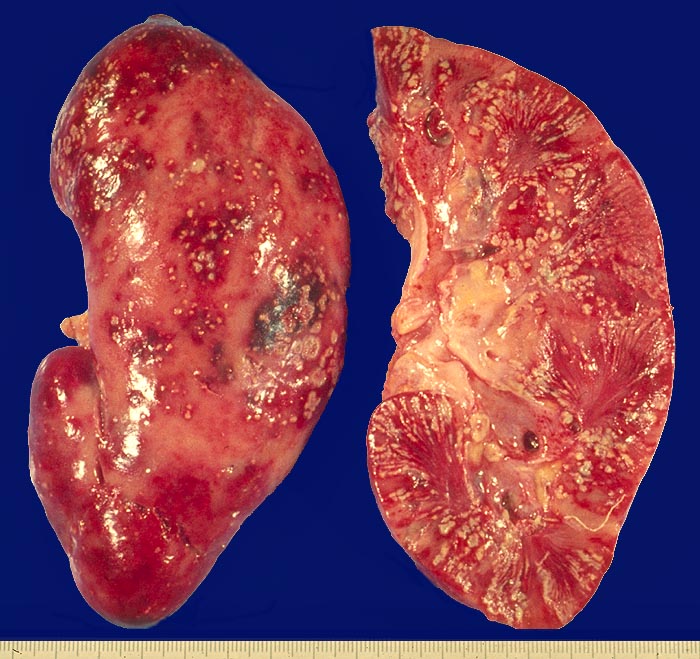

Vorkommen: